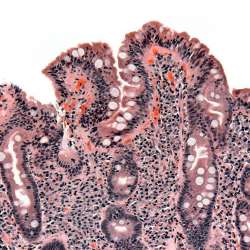

セリアック病(celiac disease)は、グルテン摂取により小腸が損傷する自己免疫疾患です。 消化器症状として、慢性的な下痢、腹痛、膨満感、栄養不良による体重減少が見られ、消化器外の症状としては、疲労 […] 読む睡眠薬 2024/12/03 00:00